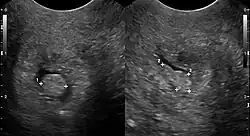

Polyp in Zervix, dargestellt mit Sonographie.